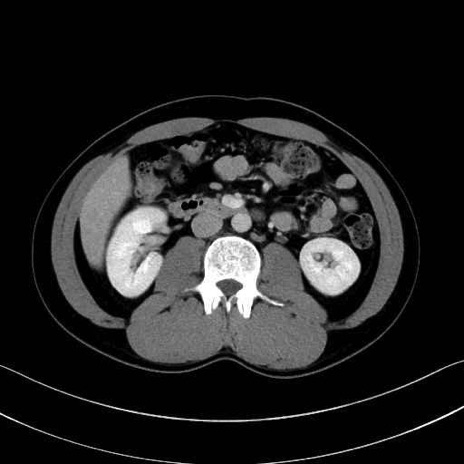

【症例】20歳代 男性 スクリーニング

脾動脈の画像解剖

■起始:典型的には腹腔動脈幹(celiac trunk)から左胃動脈・総肝動脈とともに三分岐し、脾動脈は左後上方へ向かう。

■走行:膵上縁または膵実質背側を蛇行しながら左方へ進み、膵尾部近傍で脾門へ至る。蛇行の程度は個体差が大きい。

■終枝:脾門部で複数の終末枝に分かれ、上極・下極枝や脾門枝群を形成する。胃短動脈群や左胃大網動脈はしばしば脾動脈から分岐する。